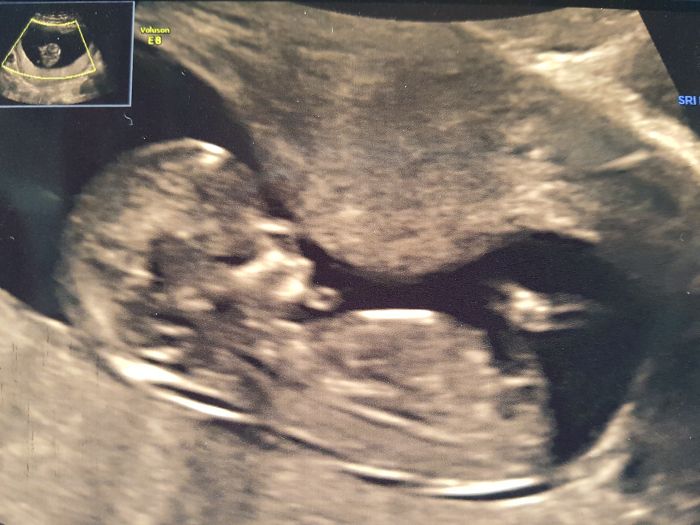

Tak ja mam za sebou uz kontrolni UTZ screening,min. utery, vsechno nastesti v poradku, vysetreni trvalo cca 15min. Dr. byl uzasny, vysvetloval a ukazoval uplne dopodrobna co a jak a kde je co. Nosni kustku, sijove projasneni, mozek, ocicka, nosik, usi, rucicky, zaludek, ledviny, poslouchali jsme srdicko, mocovy mechyr, nozicky. Byl to nadherny pocit. Slza mi i ukapla. Delal to pres brisko a muj a dcera sedeli hned vedle v sedacce a sledovali vsechno na velke obrazovce. Pri zeptani na pohlavi rekl ze tak na 70% to vidi na kluka ze se mu zda ze tam neco couha. Toho jsme si vsimli i my s mojim pri ukazovani kde je mocovy mechyr. Taky jsem to videla. Ale rikal ze to neni jeste 100% ze mi to rekne az v tom 20tt na 100%.

Dostala jsem 2 fotecky prilozim pozdeji. A podle Utz TP 7.7. hezke datum?

Marketko gratuluji k dobrym zpravickam a krasne fotecky mimiska. Taky se mi zda podle fotecek ze je to kluk